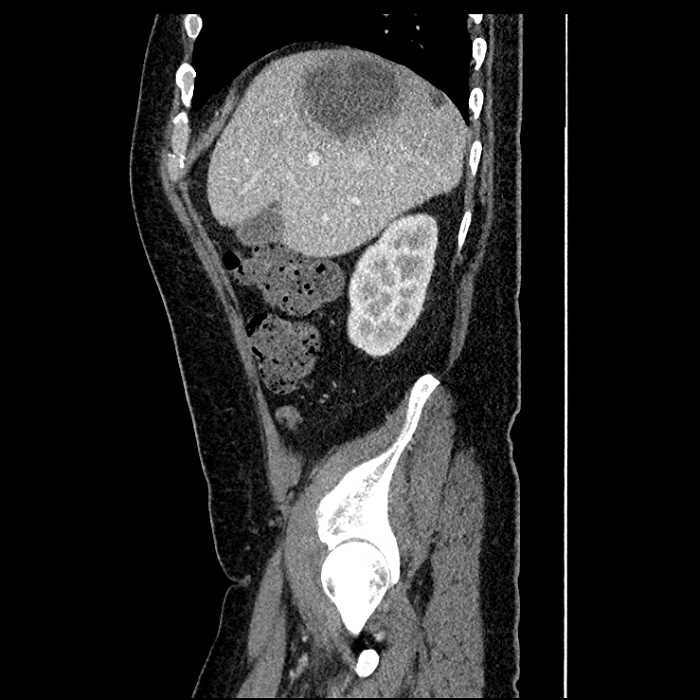

• Mild mural thickening of a segment of the sigmoid colon with adjacent fat stranding and a 1.5 cm fluid and gas collection along the tip of an inflamed diverticulum

• Loss of the normal fat plane between this collection and adjacent loops of small bowel, which demonstrate mural thickening

Acute sigmoid diverticulitis complicated by a small contained perforation and a large abscess in the right hepatic lobe. Additional small subcapsular abscesses along the anterior margin of the left hepatic lobe.

Additionally, loss of the normal fat plane between the peridiverticular collection and adjacent thickened loops of small bowel raises the potential for an enterocolonic fistula.

Hepatic abscess showing the double target sign with low density internally surrounded by a thin inner enhancing rim (red arrow) and ill-defined outer low density rim (yellow arrow). Blue arrow indicates an internal septation. Red arrows: additional smaller subcapsular abscesses. Red arrow: focal contained perforation associated with diverticulitis.